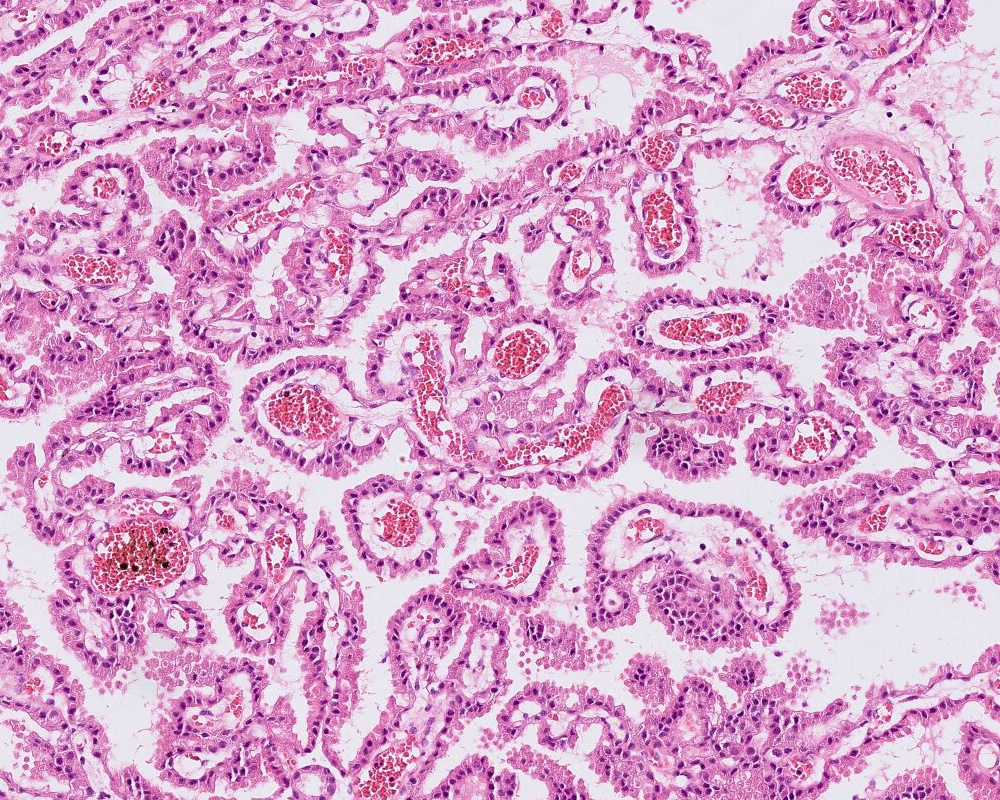

- Choroid plexus papilloma (CPP, WHO grade 1):

- Papillary (finger-like) architecture, resembling normal choroid plexus

- Single layer of cuboidal to columnar monomorphic cells

- Loss of cobblestone surface

- Mild nuclear pleomorphism, mitotic activity rare (< 2/10 high power fields), lacks necrosis

Microscopic (histologic) images

A 3 month old boy presented with restless crying and vomiting. His head size was larger than expected for his age. Imaging showed an 8 cm, lobulated, enhancing lesion in the right lateral ventricle. Histology is as above. Which of the following is true?

B. Recent studies suggest 3 distinct molecular entities based on methylation profiling, patient age and tumor location. An atypical choroid plexus tumor is shown in the image.

Choroid plexus tumors are rare intracranial tumors arising in the choroid plexus epithelium of the ventricles. They are more common in children. Histologically, they are classified into 3 categories: choroid plexus papilloma (CPP, WHO grade 1), atypical choroid plexus papilloma (aCPP, WHO grade 2) and choroid plexus carcinoma (CPC, WHO grade 3). Although any of these tumors can have CSF spread and recur following treatment, the latter is associated with poor outcome and higher recurrence rate. Recent studies have shown that CPP and aCPP are genetically similar but CPP and aCPP are genetically distinct from CPC. The CPCs are mostly driven by loss of function or mutations of tumor suppressor gene TP53 and may be associated germ line mutations (Li-Fraumeni syndrome). Furthermore, based on methylation profiling, tumor location and age, 3 distinct subgroups with prognostic significance have been described. The advances in understanding of genetics may help deliver appropriate personalized treatment.